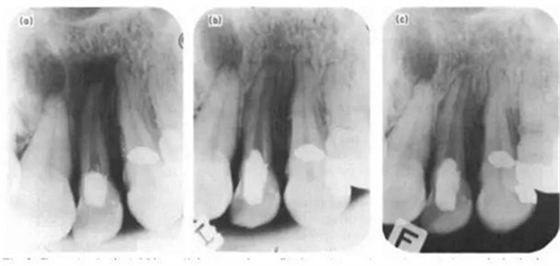

(a)-實(shí)驗(yàn)開始時(shí)22根尖片,見根尖周大面積暗影;(b)-1年復(fù)診,22根尖暗影明顯縮?。?c)-2年復(fù)診,22牙周膜間隙恢復(fù)。

在Torneck之后,還有多個(gè)反駁空管理論的研究(Davis et al. 1971; Makkes et al. 1977),其中以Klevant & Eggink(1983)的實(shí)驗(yàn)最為著名。他們對(duì)患有根尖周炎的實(shí)驗(yàn)牙在進(jìn)行根管預(yù)備后直接封閉冠部,然后進(jìn)行2年的隨訪,發(fā)現(xiàn)絕大部分的根尖暗影都出現(xiàn)了愈合,只是其速率慢于充填的根管。這個(gè)重要的結(jié)果不僅駁斥了空管理論,還對(duì)以往追求根管緊密封閉的觀念提出了挑戰(zhàn)。